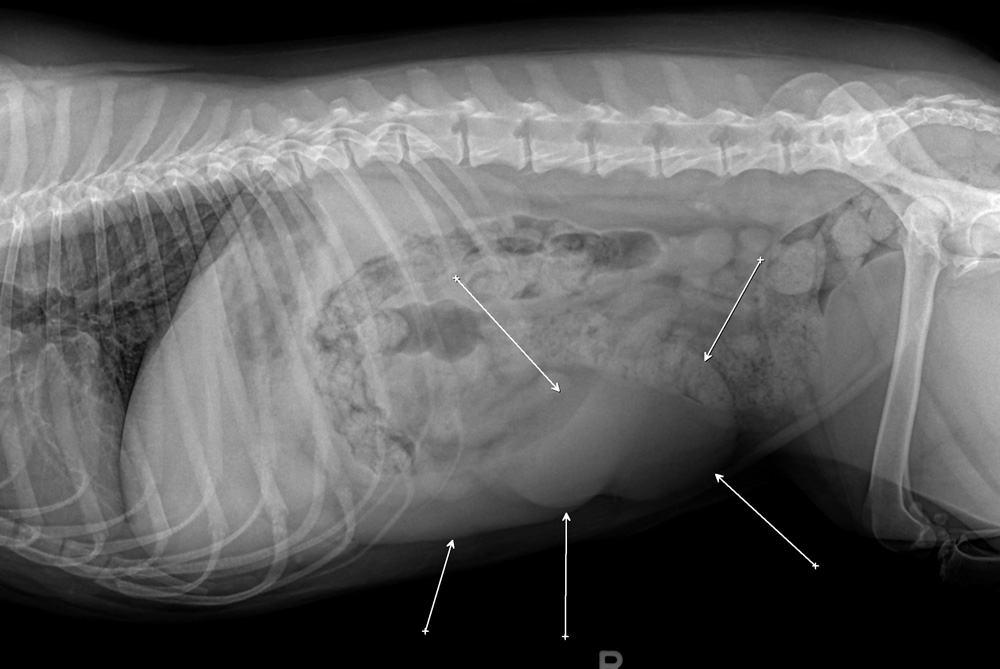

Ваш ветеринарный врач может предположить рак селезенки, основываясь на клинических признаках у животного, и частично на результатах физического осмотра. Часто помогают обнаружить опухоли рентген и УЗИ, но эти неинвазивные процедуры не всегда позволяют отличить гиперплазию от настоящего рака. В пробах крови может обнаружиться анемия, но она неспецифична, и только при некоторых опухолях в крови будут обнаруживаться раковые клетки.